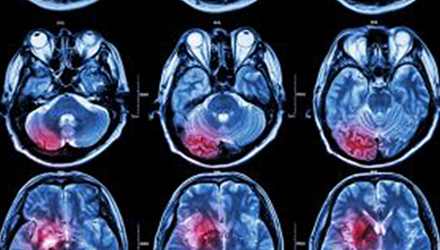

在這項(xiàng)研究中,研究人員使用功能核磁共振成像(fMRI)觀察大腦中血液含氧量的變化。研究人員首先研究了耳鳴患者和無耳鳴者的大腦活動(dòng),其目的是比較兩組受試者大腦處理情緒的方式。

在功能磁共振成像檢查中,受試者分別聽30種“愉悅”的聲音、30種“不愉快”的聲音和30種“中性”的聲音。這些聲音包括小孩咯咯笑,嬰兒啼哭,以及熱水壺?zé)_的聲音。

功能磁共振成像的結(jié)果顯示,當(dāng)暴露于情緒性聲音下,耳鳴患者大腦不同區(qū)域的活動(dòng)比沒有耳鳴者的活動(dòng)更強(qiáng)烈。接著,研究人員進(jìn)行了更深入的研究:耳鳴患者的大腦活躍性和耳鳴嚴(yán)重程度的關(guān)系。

調(diào)查結(jié)束后,再進(jìn)行功能核磁共振成像檢查。第二輪功能核磁共振成像顯示,那些耳鳴較輕的患者實(shí)際上使用了大腦不同的區(qū)域來處理情緒信息。

傳統(tǒng)觀點(diǎn)認(rèn)為,大腦中的扁桃體是處理情緒的關(guān)鍵,但此次研究發(fā)現(xiàn),那些不被耳鳴困擾的患者實(shí)際上使用更多大腦額葉來處理情緒。這類患者額葉活動(dòng)更顯著的原因是,額葉通常更多地用于注意力、計(jì)劃和沖動(dòng)的控制。